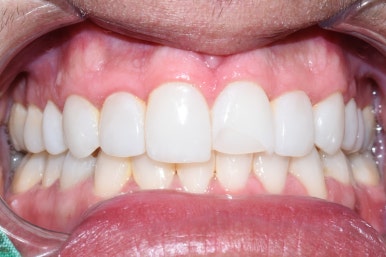

Case 4.

이건 치아가 반 이상 날아가버렸는데요 ㅠㅠ

이분도 외국인이라 본인나라에서 크라운을 하기로 하고

한국에서 급하게 레진으로 치료하고 관광사진 등을 찍을 수 있게 해드렸습니다.